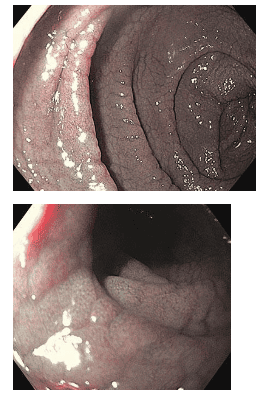

Hình ảnh bên trái trình bày các nếp van tá tràng với các vết nứt có thể nhìn thấy và hình dạng dạng nốt. Quan sát kỹ hơn các nếp gấp này cho thấy không có nhung mao. Cả hai hình ảnh đều được tạo bằng chế độ quan sát NBI.

Với sự phát triển của các kĩ thuật nội soi, ngày càng ghi nhận nhiều hình ảnh nội soi gợi ý bệnh Celiac từ đó giúp các bác sĩ nội soi định hướng tiến hành sinh thiết dễ dàng hơn.

Hình ảnh điển hình trên nội soi ở đoạn xuống của tá tràng sau khi bơm hơi căng bao gồm: giảm số lượng nếp gấp vùng niêm mạc tá tràng (nếp gấp Kercking), niêm mạc tá tràng thô, có thể quan sát được mạng lưới mạch máu dưới niêm mạc (teo niêm mạc), có thể thấy các khía, rãnh sâu, có dạng khám, lần sần hoặc có hình ảnh lát sỏi.